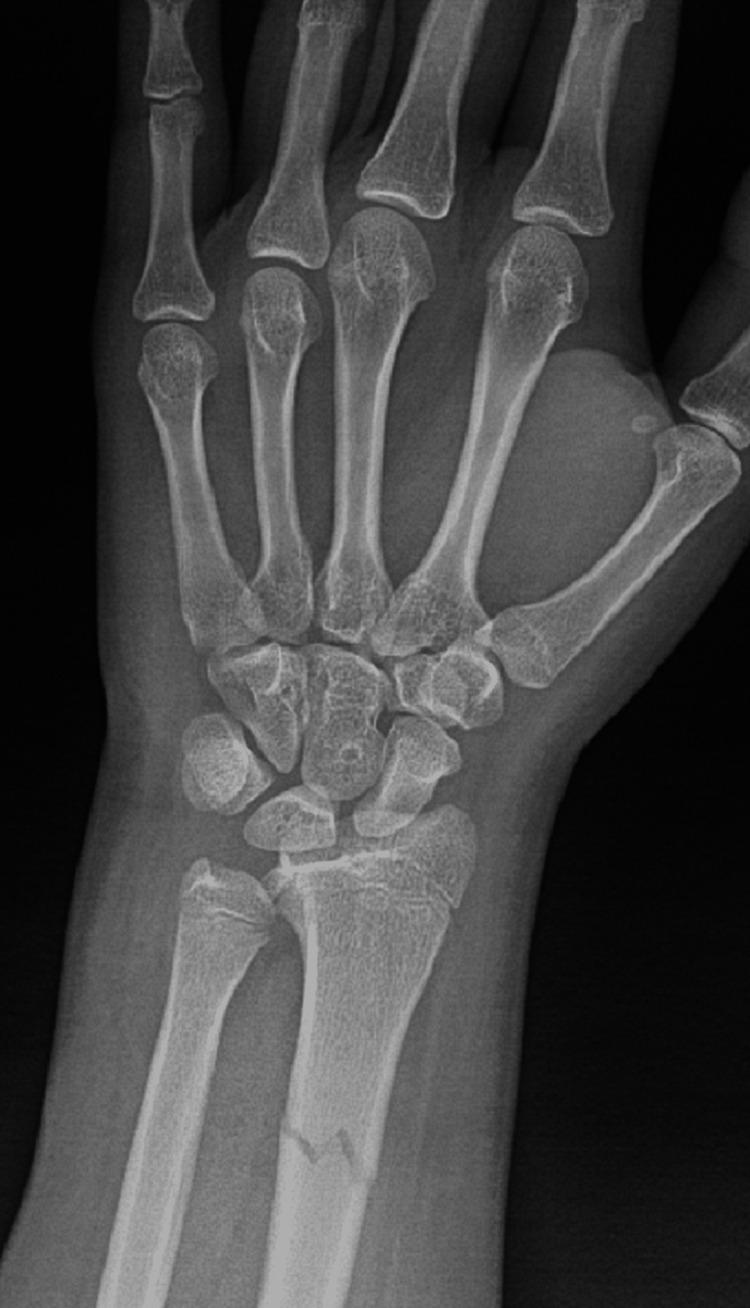

Fractures of the forearm are common among children and adolescents. Radial shaft fracture with dislocation of the distal radioulnar joint (DRUJ), called Galeazzi fracture, is unusual in pediatrics. The Galeazzi-equivalent fracture is a variant of the classic Galeazzi fracture that occurs in children and adolescents. It is a radius fracture associated with a distal ulnar displaced physeal injury without dislocation of the DRUJ. Our patient was a male, aged 15 years, who visited our emergency department after falling off a scooter onto his left hand. Left wrist X-rays showed a displaced Galeazzi-equivalent fracture. After a trial of close reduction, an X-ray showed a displaced and unstable fracture pattern. The patient was subsequently hospitalized for surgical intervention. Open reduction and internal fixation (ORIF) with a plate and screw were used for the radius fracture. The ulna fracture was irreducible; therefore, ORIF with two crossed smooth Kirschner wires (K-wires) was performed. Complete bone union was achieved, and he had a normal range of motion six months postoperatively. The patient is now able to perform daily and sports activities. At two-year follow-up, complications such as DRUJ instability or joint deformity did not occur. In conclusion, open reduction is desired for patients with malalignment or older patients who have a lower potential for sufficient bone remodeling. Regular serial follow-up sessions are required to assess growth arrest and the occurrence of other complications.

前臂骨折在儿童和青少年中很常见。桡骨干骨折合并下尺桡关节(DRUJ)脱位,即盖氏骨折,在儿科中并不常见。类盖氏骨折是经典盖氏骨折的一种变体,发生于儿童和青少年。它是一种桡骨骨折,伴有尺骨远端骨骺移位损伤,而DRUJ无脱位。我们的患者是一名15岁男性,骑滑板车时左手着地后前来我院急诊科就诊。左手腕X线片显示为移位的类盖氏骨折。试行闭合复位后,X线片显示骨折移位且不稳定。患者随后住院接受手术治疗。桡骨骨折采用钢板螺钉切开复位内固定(ORIF)。尺骨骨折无法复位;因此,采用两根交叉光滑克氏针(K针)进行ORIF。术后6个月实现了完全骨愈合,患者活动范围正常。患者现在能够进行日常和体育活动。在两年的随访中,未出现DRUJ不稳定或关节畸形等并发症。总之,对于骨折对位不良的患者或骨重塑潜力较低的年长患者,需要进行切开复位。需要定期进行系列随访,以评估生长停滞和其他并发症的发生情况。